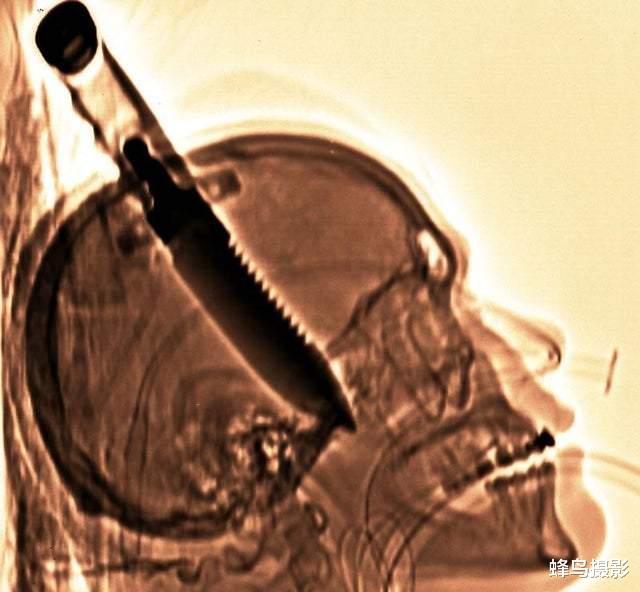

1998年 , 迈克尔希尔在朋友家被刺伤了大脑 。 令人惊奇的是 , 他居逃过一劫很快就出院了 , 但这把刀对他的记忆造成了永久性损害 。 这把刀也成为史以来 , 从人类大脑中取出的最大物体 。